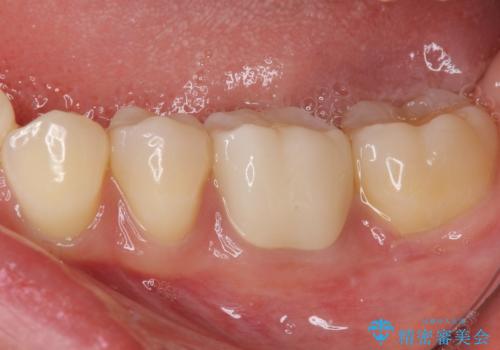

- 近医にてセラミックを装着した左下の奥歯に痛みが続いたとのことで来院された患者様です。

診査の結果、既に歯の神経は失活していたおり、排膿路が認められ、叩いたり触ったりしたときの痛みも確認されました。

根管治療を行った後にオールセラミッククラウンにて補綴することとしました。

初回の治療後には歯肉に認められた排膿の出口などの症状は消えていました。

補綴後6ヶ月経過しレントゲンを撮影したところ、遠心の歯根付近の病変が消失していることが確認できました。